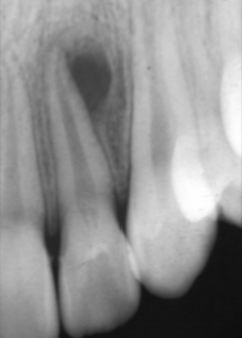

Describe this Radicular Cyst

Epicenter at apex (usually evidence of dental disease or trauma)

Well-defined, corticated

Lucent

Circular

Resorption, Displacement, Expansion (effect on adjacent structures)

Why is this Radicular cyst less circular/oval in this case?